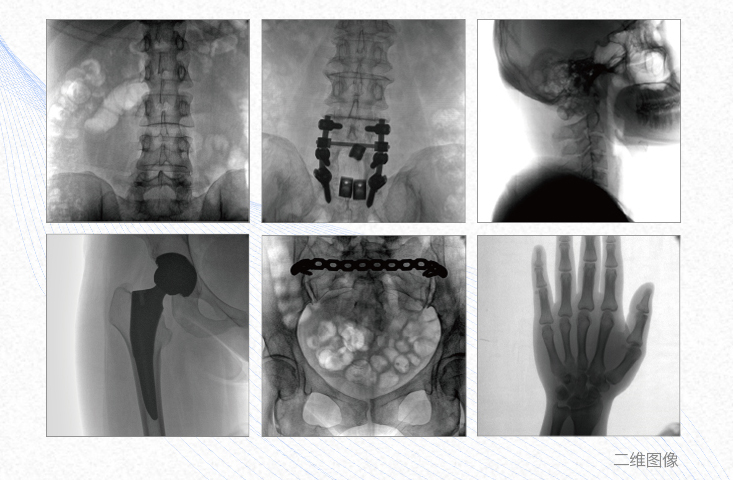

有效重建復(fù)雜的脊柱三維模型,提供準(zhǔn)確的二維、三維圖像,提高螺釘植入的準(zhǔn)確性,縮短手術(shù)時(shí)間,減少并發(fā)癥的概率,降低輻射的攝入。

例如骨盆骨折內(nèi)固定術(shù),可術(shù)中三維重建髖臼關(guān)節(jié)面,準(zhǔn)確定位并植入螺釘,有效縮短螺釘植入的時(shí)間和透視暴露時(shí)間,減少術(shù)中及術(shù)后并發(fā)癥發(fā)生的概率。

主要應(yīng)用于肩關(guān)節(jié)、肘關(guān)節(jié)、髖關(guān)節(jié)、膝關(guān)節(jié)的關(guān)節(jié)置換及解剖復(fù)位的定位。它可以準(zhǔn)確地置入假體,減少輻射時(shí)間,降低輻射劑量。

例如治療先天性脊柱側(cè)后凸畸形,可有效引導(dǎo)術(shù)者植入后路螺釘并切除半錐體,達(dá)到滿意的截骨矯正效果。

提供更大的術(shù)中三維成像視野,采集更多圖像信息,可一次拍全全段頸椎、全段腰椎、七節(jié)胸椎、雙側(cè)骶髂關(guān)節(jié)、股骨頭及單側(cè)盆骨。